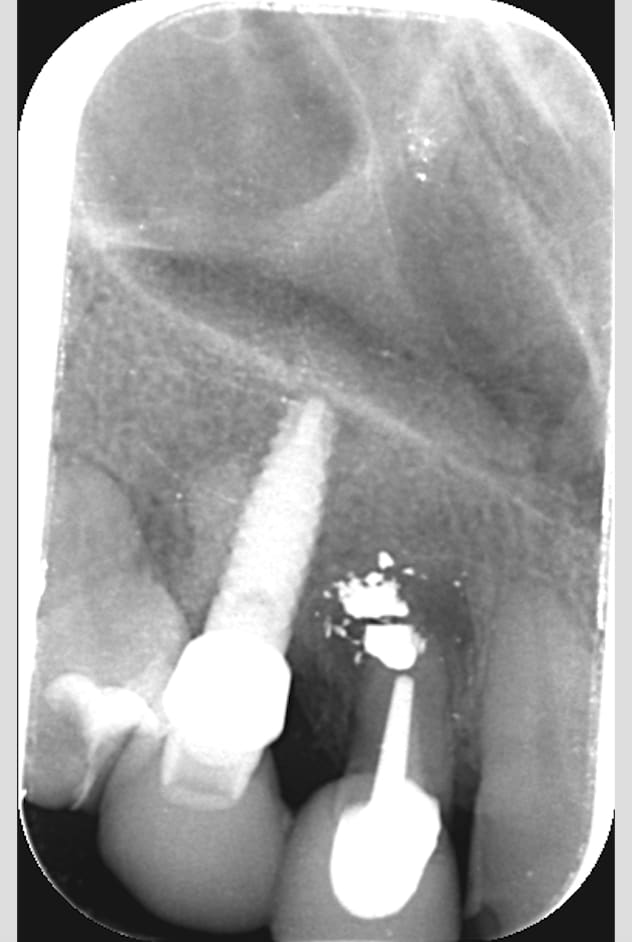

voilà le cas d'une patiente qui présente un abcès sur 12 avec fistule, (12 qui a déjà eu une résection et MTA il y a 5 ans)

j'ai prévu de faire exo de la 12 avec curetage de l'abcès et du MTA pour bien tout nettoyer

un scan pour ce cas est un minimum surtout vu l angulation de la radio et du délabrement au niveau de l apex ....